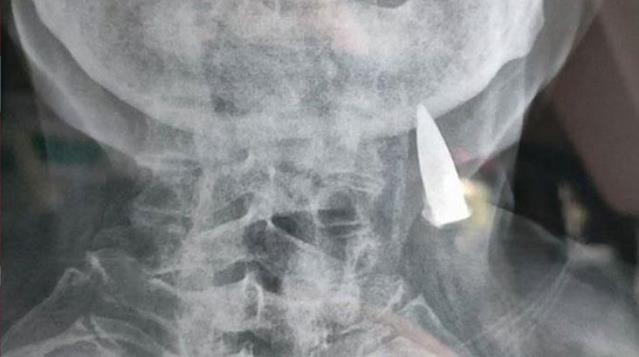

Baş ağrısı şikayetiyle gittiği hastanede röntgen çektiren 95 yaşındaki Zhao He'nin sonuçları alan doktorlar gördükleri detay karşısında hayrete düştü. Çin ordusu adına İkinci Dünya Savaşı'nda görev alan adamın boynuna saplı bir kurşun bulan doktorlar bu kurşunun tam 70 yıldan bu yana adamın boynunda durduğunu belirledi.

Zhao He'nin röntgenini kontrol eden doktorlar, karşılaştıkları manzarayla dehşete düştü. Çünkü adamın boynuna saplı bir halde kurşun tespit edildi. Adamın görüşüne başvuran doktorlar, bu kurşunun tam 70 yıldan bu yana adamın boynunda olduğunu tespit etti.